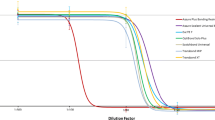

Human gingival fibroblasts and HPF were exposed to the monomers/comonomers as described above in combination with H2O2 (final H2O2 concentration 0.06 or 0.1 mmol/l, respectively). At these H2O2 levels no toxic effects in the XTT test were observed on HGF or HPF, which received H2O2 only (without monomers/comonomers). Therefore in this test system these H2O2 levels correspond to the EC0 of H2O2 in HGF (Fig. 1) or HPF. H2O2 was diluted with Quantum 333 medium.

The EC50 values of tested compounds in HGF are presented as mean ± s.e.m. in Table 1. The EC50 value of H2O2 (without comonomer/monomer addition) was 0.36 mmol/l (Table 1; Fig. 1).

In the following study the human oral cells HGF and HPF were used. No significant (P < 0.05) differences in all the results were found when HGF was exposed to these substances as compared to HPF. These results indicate that individual cell differences between HGF and HPF are only of minor relevance for this test system. When HGF was exposed to H2O2 only (without monomers/comonomers) the EC50 value was 0.36 ± 0.04 mmol/l (Fig. 1). For testing additive effects of monomers/comonomers in combination with H2O2 a non-toxic dose level of H2O2 must be used. The H2O2 concentrations of 0.06 or 0.1 mmol/l, respectively, were chosen for these experiments because at these H2O2 levels no toxic effects were observed in HGF or HPF in this test system. Therefore the H2O2 concentration levels of 0.06 or 0.1 mmol/l correspond to the EC0 value for H2O2 in these cells in this test system. A H2O2 concentration higher than 0.1 mmol/l is not advisable, because at 0.2 mmol/l it is not possible to distinguish between a possible monomer/comonomer synergistic and a toxic effect caused by H2O2 itself (see Fig. 1).